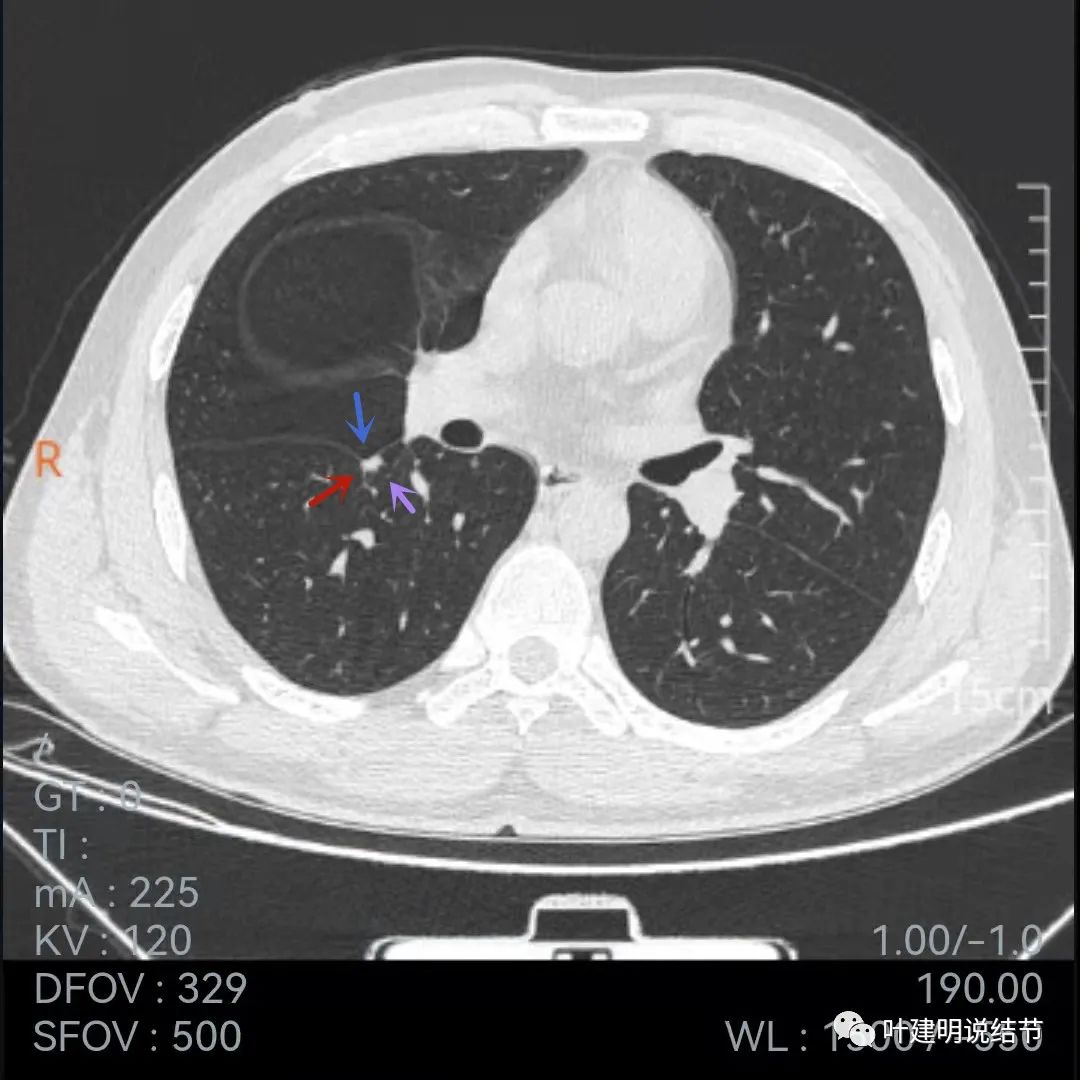

再看下面2020年7月的平扫片子:

非薄层的看,病灶还是小结节,实性,边缘似乎比前一年略有毛糙,胸膜轻微牵拉,黄色箭头所指似乎病灶中央的密度比周围部分略低,会不会是肉芽肿性炎伴有少许坏死?